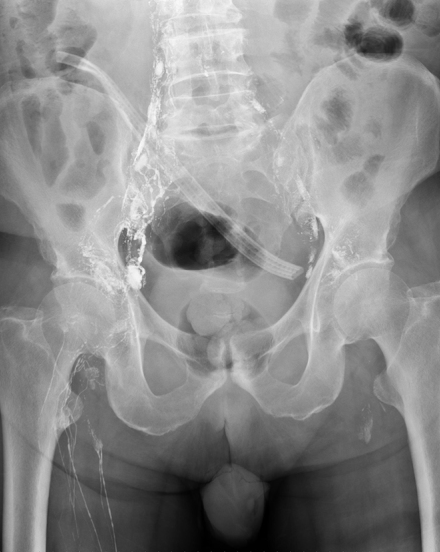

Peritoneovenous shunt in another patient with decompensated hepatic cirrhosis (Courtesy Dr. V. Penopoulos)